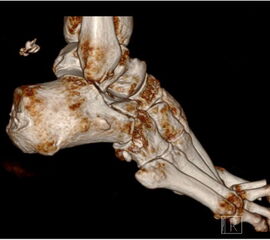

Knöcherne Ausrisse lassen sich in der seitlichen Röntgenaufnahme des Sprunggelenkes ausschließen oder beweisen (Abb. 5). Eine Sonderform bilden hier die Entenschnabelfrakturen des Kalkaneus.

Abbildung 5

Der geübte Untersucher kann anhand des seitlichen Röntgenbildes die Diagnose einer Achillessehnenruptur stellen. Die Konturen des Kager-Dreiecks – gebildet von der ventralen Begrenzung der Achillessehne, der posterioren Tibiakante und der kranialen Kalkaneuskortikalis – verstreichen im Rupturfall (Kager 1939). Die MRT- Diagnostik spielt für die Primärdiagnostik der frischen Achillessehnenruptur eine untergeordnete Rolle und ist im Normalfall nicht notwendig. Anders verhält es sich bei den chronischen Rupturen. Hier ist die MRT ein wichtiges Diagnostikum insbesondere in Hinblick auf die Beurteilung der Sehnen- und Muskeldegeneration (Abb. 6).